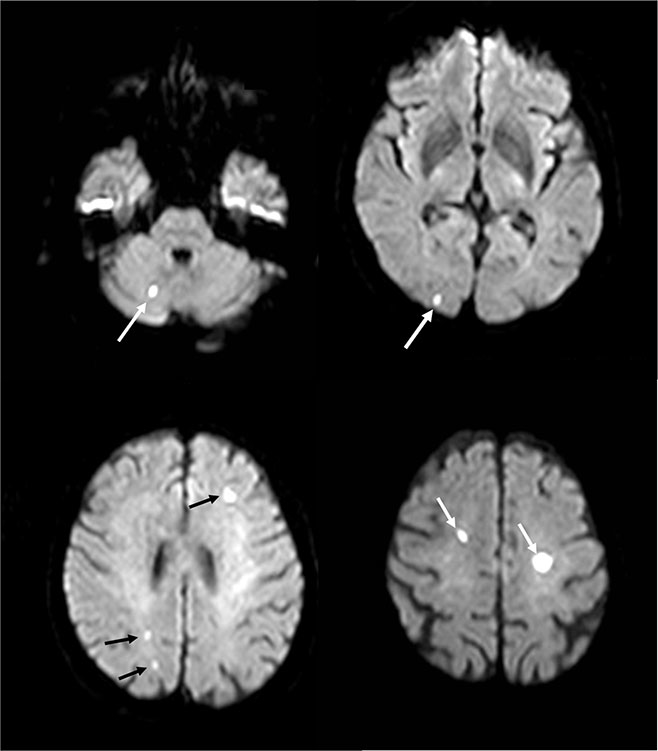

Figure 3

Silent bilateral cerebrovascular emboli after transcatheter aortic valve implantation. Such diffuse, bihemispheric ischaemic lesions can be detected by MRT in 68–77% of patients after TAVI.

To investigate silent cerebrovascular embolism, Kahlert et al. performed diffusion-weighted magnetic resonance tomographies (MRT) in patients undergoing TAVI (n = 32) and open surgical aortic valve replacement (n = 21) [45]. After a median of 3.4 days post procedure new foci were found in 84% of patients undergoing TAVI (fig. 3 ). There was no clinical stroke in the TAVI group (but one stroke in the SAVR group), and there was no difference between the balloon-expandable Sapien valve (Edwards Lifesciences Inc, Irvine, CA) and the self-expanding CoreValve (Medtronic Inc., Minneapolis, MN). At 3 months the majority (80%) of the acute lesions had resolved. These findings were confirmed by other studies, showing that diffuse bihemispheric ischaemic lesions can be detected by MRT in 68–77% of patients after TAVI [46–49]. No differences between the transfemoral and the transapical approach were found, although some have suggested that transapical TAVI may result in less trauma to the aortic valve and aortic arch, since less manipulation of catheters is needed [46, 50]. However, there is no evidence to support this. The incidence of clinically relevant strokes correlated with the number and size of lesions on MRT in some [49] but not all studies [47]. Therefore the clinical significance of these lesions remains unclear, although evidence from the surgical literature indicates that multiple, apparently silent, cerebral infarctions increase the risk of neurological dysfunction and cognitive decline [51].